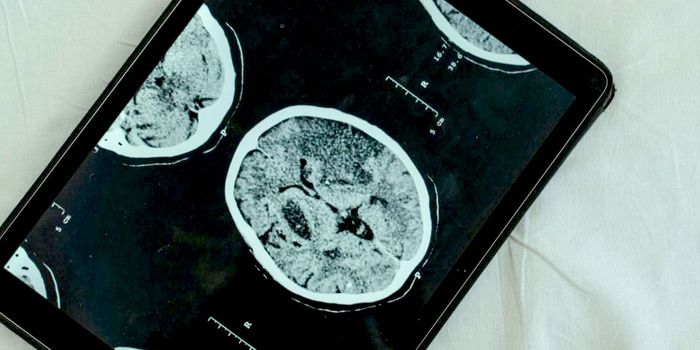

FEB 09, 2025CancerGlioblastoma (GBM), an aggressive form of cancer that grows in the brain or spinal cord, occurs at an incidence rate of ...